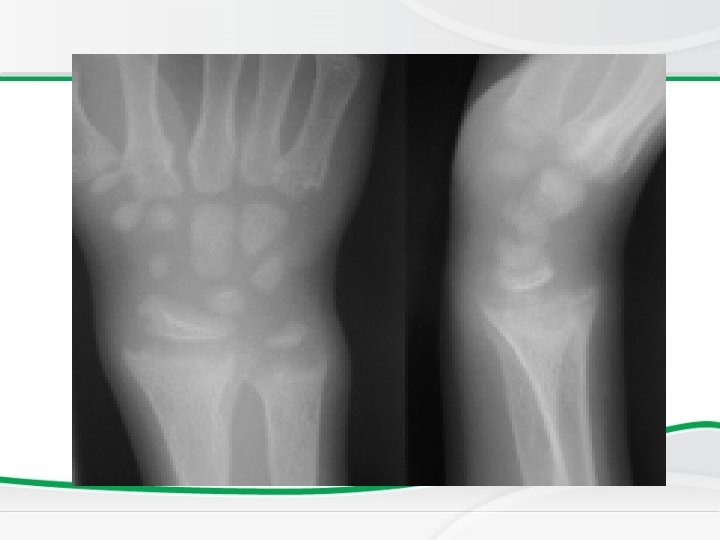

Investigations, • BASIC INVESTIGATIONS TO CONFIRM RICKETS • • Low or normal serum Ca Low phospherus High alkaline phosphatase X rays of ends of long bones at knees or wrists • Shows Widening, fraying, cupping of the distal ends of shaft. • Vit D level low • Parathyroid hormone high

Newborn Screening Rickets • Radiology changes

Genu valgus Wrist cupping Tri radiate pelvis Looser’s zones Wrist widening Wide metaphysis